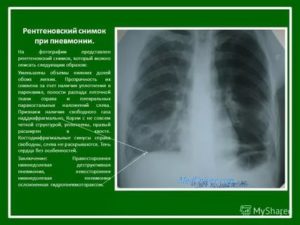

Рентген легких при пневмонии является не только методом выявления заболевания, но и способом контроля динамики его течения при терапии. Существует несколько форм воспалительных изменений легких в зависимости от области распространения патологического процесса, рентгеносемиотика которых отличается.

Рентген-снимки при крупозной пневмонии характеризуются следующими синдромами:

- Обширное (тотальное) снижение прозрачности легочной ткани.

- Субтотальное затемнение – при локализации воспаления в пределах одной или двух долей легких.

- Ограниченное затемнение – инфильтративные изменения легочной ткани, не выходящие за пределы сегмента.